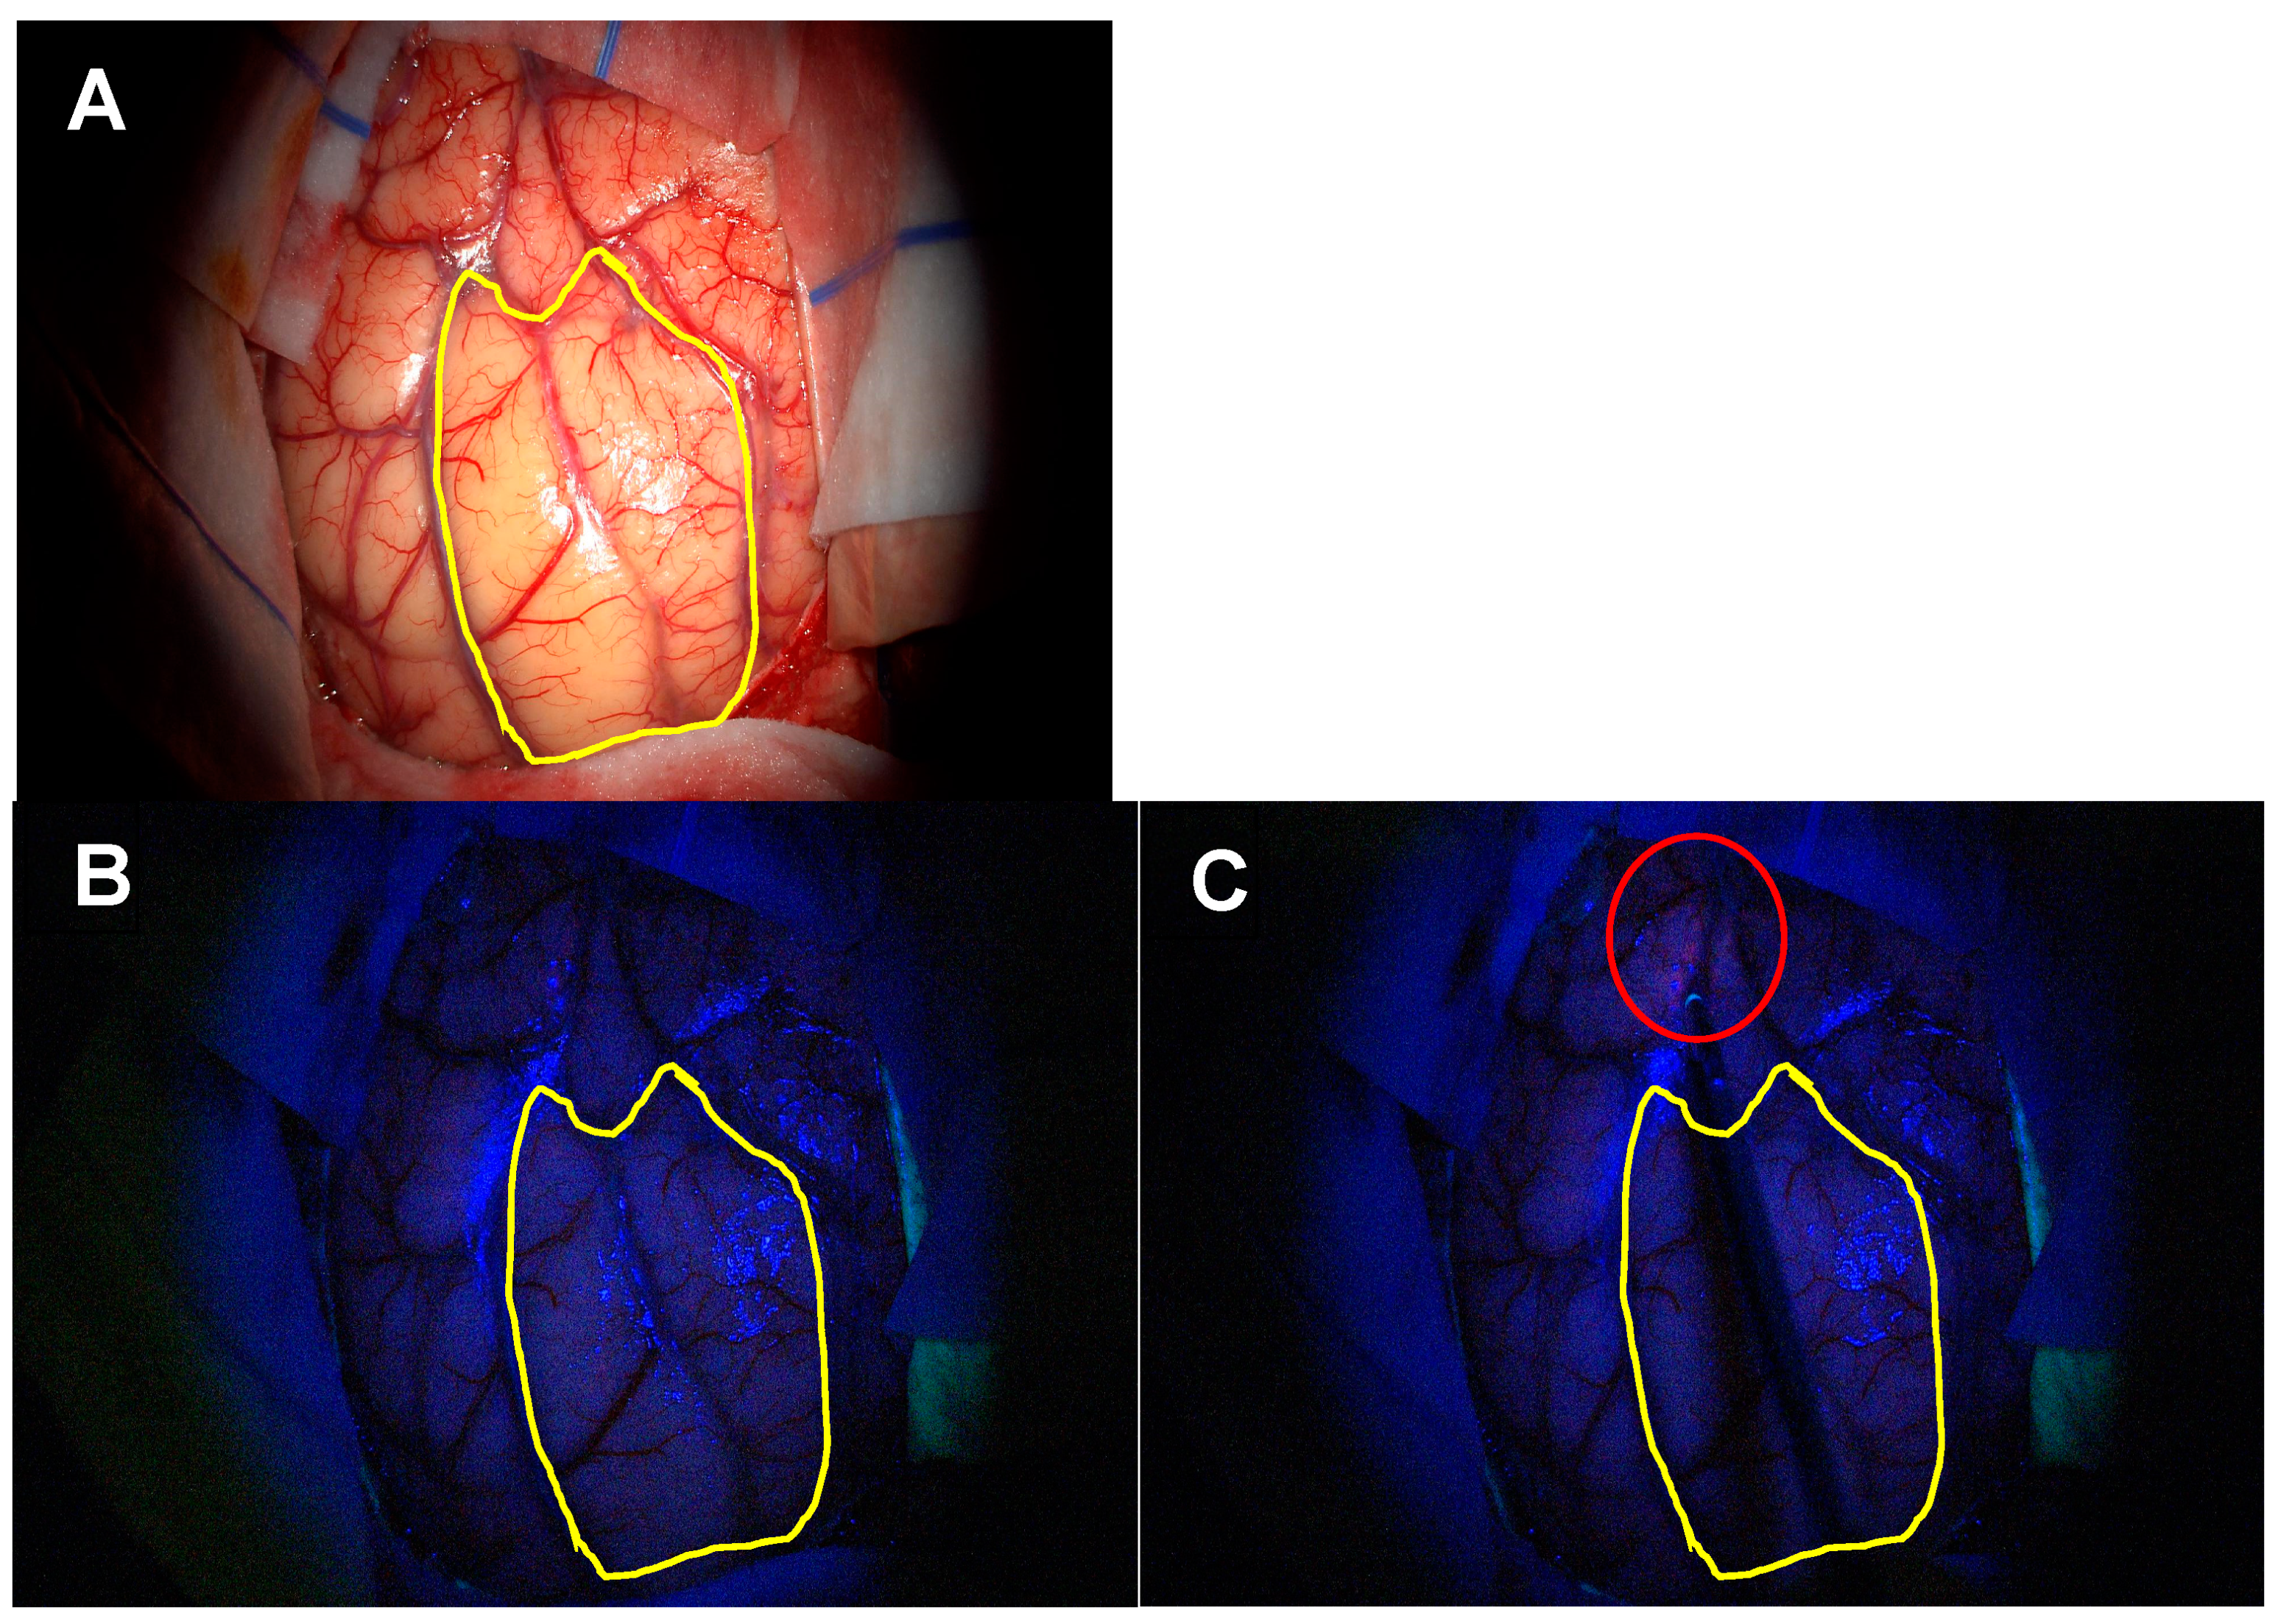

3.1.2. Extent of Resection (EoR) in Patients Eligible for Gross Total Resection